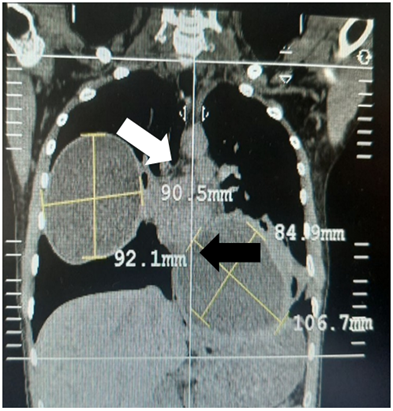

A 24-year-old male from Puerto Maldonado with a history of insulin-dependent Diabetes Mellitus I (DM1) for 19 years, diabetic retinopathy, arterial hypertension and bilateral pulmonary hydatidosis for 2 years; He arrived at the emergency service due to a 3-month illness period characterized by moderate chest pain and dyspnea on medium efforts, which increased in the last 15 days; A physical examination was carried out, where the abolition of the vesicular murmur was observed in the middle 1/3 of the right hemithorax and, based on the left hemithorax, his hospitalization was subsequently indicated for further auxiliary tests. A Computed Tomography of the Thorax was indicated (Figure 1) where images suggestive of pulmonary hydatid cysts were observed and then an evaluation of the specialty of Thorax and Cardiovascular Surgery was requested for the management of the patient. It was decided that the patient should enter surgery at two different times to undergo surgical treatment; days later, the patient underwent the respective preoperative examinations of pneumology (Pneumological Risk III/IV), cardiology (Cardiological Risk III/IV) and anesthesiology (ASA III) and the technique of the first operation between a Cystectomy vs Lobectomy was evaluated; While waiting for the date of the first surgical intervention of the left pulmonary cyst, since it could become complicated, the patient was managed with Captopril (25mg PRN at BP ≥140 / 90), insulin NPH 20U SC in the morning and Crystalline Insulin 5U later of meals, despite treatment, the patient had poor glycemic control (180-340 mg/dl), which is why the dose of NPH insulin is increased to 15U in the morning and 10U at night, after evaluation by endocrinology.

Figure 1 Multislice Spiral Tomography shows 02 cystic images, one in the right hemithorax with liquid content (white arrow) and another in the left hemithorax with liquid content (black arrow) of 9.05 cm x 9.21 cm and 8.49 cm x 10.67 cm respectively, thus as a pneumoperichst suggestive of a cystic lesion in the process of rupture.